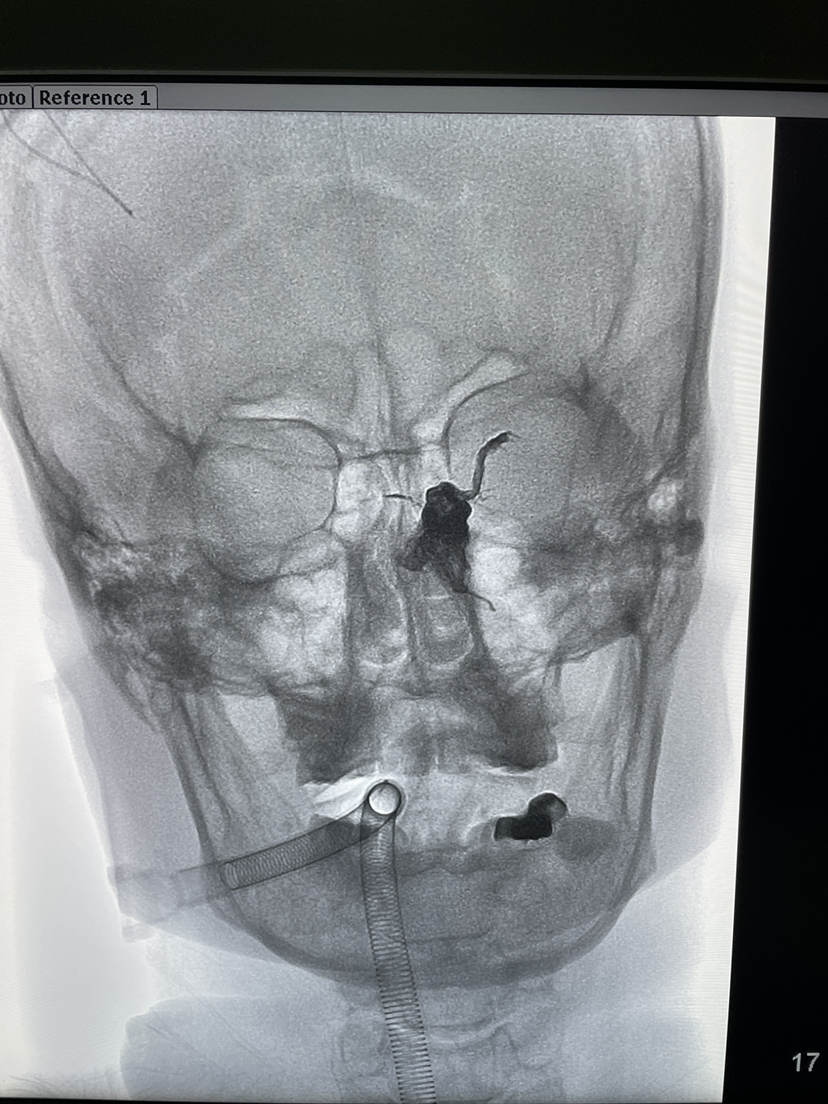

方案一:左侧静内静脉-岩下窦-左侧海绵窦(双微导管)

方案二:左侧颈外静脉-岩下窦-左侧海绵窦

方案三:右侧颈内静脉-岩下窦-右侧海绵窦-海绵间窦-左侧海绵窦(无路)

很快打脸了。左侧没有颈内静脉,另外静脉无法上到岩下窦🥹🥹🥹🥹

更弦更张,从右侧入路,天知道我经历了什么(我只是下定决心不碰瘘)

7-30弹簧圈栓塞后。胶水慢慢注入,真的是漫长的过程

瘘口封堵满意,证实瘘口其实再在左侧海绵窦上,手术结束

术后患者清醒满意,颅内杂音消失